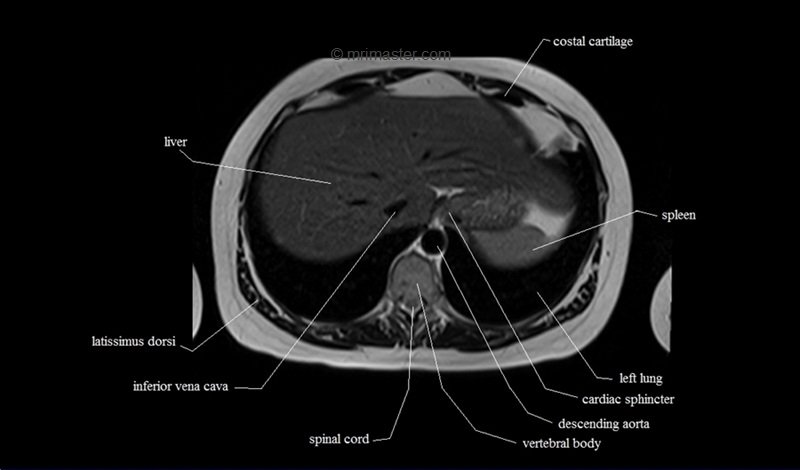

MRI Axial Cross Sectional Anatomy of Chest

This MRI chest (thorax) axial cross sectional anatomy tool is absolutely free to use. Use the mouse scroll wheel to move the images up and down, or alternatively, use the tiny arrows (→) on both sides of the image to navigate through the images. For a more detailed view, double-click the image to view it in full screen, and use the menu in the top right-hand corner to view individual slides or play them in a loop.